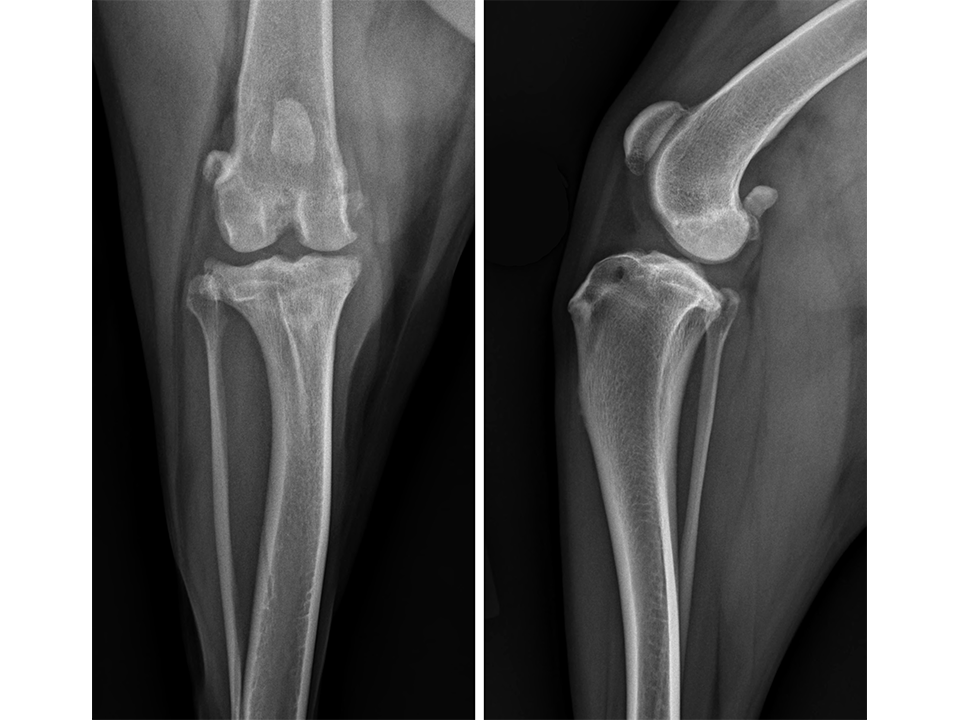

A 2-year-old labrador retriever presented for assessment of a moderate intermittent weight-bearing left pelvic limb lameness of four months duration. Orthopedic examination revealed moderate stifle joint effusion, medial buttress formation of the proximal tibia, crepitus, and a moderate pain response upon manipulation and extension of the stifle joint. Joint laxity was evident with both cranial drawer and CrTT. There was also mild effusion palpable in the right stifle joint, but this was otherwise unremarkable upon examination.

Radiographs of both stifle joints (Fig 5 and 6) revealed bilateral moderate joint effusion and minimal bony proliferation along the distal aspect of the patella. Considering the clinical findings, these radiographic signs were interpreted as minimal bilateral osteoarthritis secondary to CrCL disease.

The left stifle was evaluated for a Tibial Tuberosity Advancement (TTA) and the owner was advised that stabilization of the right stifle would likely be required in the future. Preoperative TTA planning was conducted using anatomic tibial plateau and patellar tendon angle landmarks. A 13.5 mm wedge and a size 6 plate were selected.